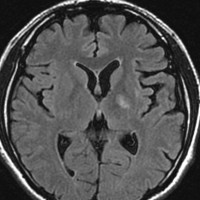

何にもしないで治ってしまう

我慢に我慢を重ねて,放射線治療後16ヶ月後です。腫瘍は消失しましたし,左片麻痺も良くなって,少年は野球ができるようになりました。

pseudoprogressionのときに腫瘍摘出術をしていたら,重度の障害が残ったでしょう。